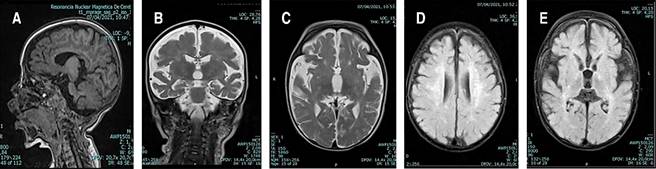

Se descartó neuroinfección y se suspendió el esquema antimicrobiano. Se realizó RMC, cuyas imágenes se presentan en la Figura 2. También se realizó electroencefalograma por presencia de posturas anormales persistentes, en el cual se reportó lentificación moderada de los ritmos de fondo, posiblemente relacionados con el uso de medicamentos (benzodiacepinas o barbitúricos), pero sin actividad ictal.

Figura 2: Resonancia magnética cerebral. A) Corte sagital T1 donde se evidencia adelgazamiento del cuerpo calloso, pérdida de volumen generalizad<a supra e infratentorial con ampliación de los espacios subaracnoideos y cisternas. B) Corte coronal T2. C) Corte axial T2. D y E) Corte axial T2/FLAIR se aprecia alteración de la sustancia blanca difusa desde la corona radiada e hiperintensidades del tracto corticoespinal.